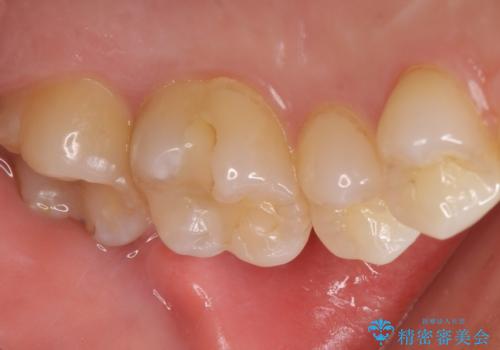

精査したところ、奥歯に充填された保険内のコンポジットレジンの適合が悪いことにより、汚れがたまりやすい状態でした。

不適合なレジンを除去し、セラミックインレーによる治療を行いました。(右上76左上67右下7の計5本)

インレーの種類:セラミックインレー e-max press